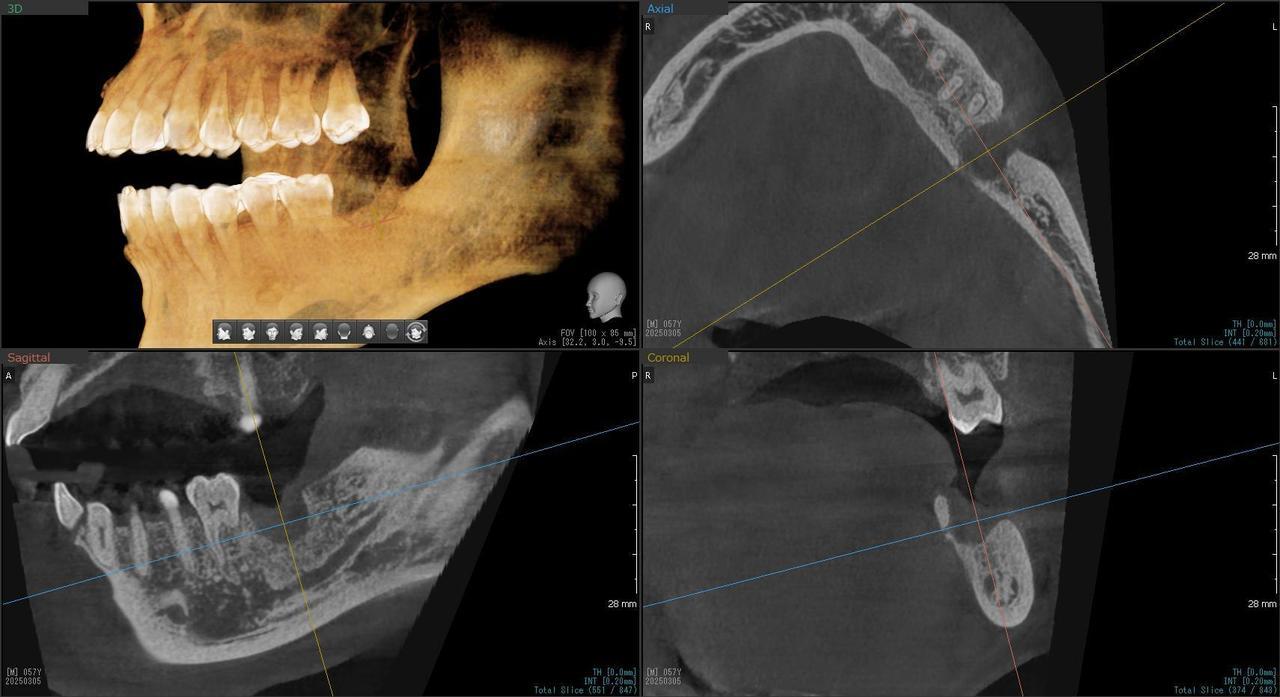

1.左上3番 インプラント抜歯即時埋入即時荷重(手術当日に抜歯を行い、当日に仮歯を入れています。)、左上4番 3ユニット式ブリッジが入るまでの暫間インプラントを埋入して当日に仮歯の装着。 左上5 既存骨3mmのグラフトレスサイナスリフト。最終補綴は、3ユニットジルコニアブリッジで治療を終えた症例

患者様の症状としては、左上5番の排膿と重度の歯の動揺、重度の骨吸収、左上3番、中程度の骨吸収と中程度の歯の動揺、自発痛がありました。

治療法としては、左上3456にブリッジ治療が行われていたが、左上5の骨吸収と排膿を認めるために抜歯を行った2か月後に、患者様は、インプラント治療を希望。左上3の骨吸収と動揺も認めていたために、左上3を保存しても将来的な抜歯が予想されたため、左上3抜歯しての左上345の3ユニット式ブリッジ治療の計画を立てインプラント手術を行っています。患者様は、前歯がないことを気にされていたため、左上3番の抜歯と同時の仮歯製作と左上4番暫間インプラントにての仮歯製作を手術と同時に行っています。また、左上3番の歯肉退縮を予防するために、ご自分の歯の一部を温存するルートメンブレンテクニックを行っています。左上5に関しては、既存骨が3mm程度しかないので、グラフトレスサイナスリフトを施行して、表面の骨吸収した部分に骨補填材填入して、ボリュームを維持させていただいています。最終的な3ユニットブリッジは、ジルコニアで製作しています。補綴物の製作に関しては、オールデジタルで行っています。

治療結果は、患者様の希望通り、見えるところの歯がない状態なく、治療を終えることができたことと、また、グラフトレスサイナスリフトを施行することにより、従来のサイナスリフトを施行した場合と比較して、6時か月以上早く治療を終えることができたことと、ルートメンブレンテクニックを行うことで、歯肉退縮を少なくでき、自然な見た目で、最終補綴物を装着できました。従来のGBRやサイナスリフトを行わなかったことにより、短時間で、低侵襲に治療を終えることができ、審美面と機能面の回復を行うことができました。

治療の期間・回数:4か月、10回

治療の価格:814,000円(税込)